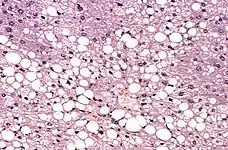

La fijación se hace por el método de tejido fijado con formol al 10 % (en la gran mayoría de los casos), también se usa como fijador mezclas como el líquido de Bouin, o bien de la sección congelada para las operaciones con biopsia extemporánea (proceso extremadamente rápido para obtener el resultado cuando la cirugía está en curso y el resultado influirá qué curso va a seguir la intervención quirúrgica). La función de este procedimiento es mantener la muestra evitando que se produzca la autolisis (autodestrucción celular) además de permitir que los tejidos permanezcan sin cambios luego de subsecuentes tratamientos.[3] La cantidad de líquido fijador a utilizar debe ser aproximadamente 10 a 20 veces el volumen de la muestra. El tiempo de fijación es de 1 mm de tejido por hora.[4] A mayor tamaño de la pieza debe ser mayor cantidad de fijador. Por ejemplo, para conservar correctamente un cerebro se debe colocar inmediatamente en solución de formol puro 2 horas, luego al 80 % 2 horas más, al 60 % 4 horas, al 40 % durante 6 horas, luego al 20 % 24 horas para terminar el proceso de fijación al 10 % de formol durante 72 horas.

En cuestión a lípidos, el formol fija algunos lípidos complejos y no saturados, pero no actúa sobre las grasas neutras, y los fosfolípidos tienden a difundir lentamente en el fijador, por lo que el uso del formol en lípidos no es recomendado.[4]

El método de tinción de rutina es el denominado como Hematoxilina - Eosina (H-E). La hematoxilina es un colorante nuclear, y la Eosina, citoplasmático. También existen las denominadas técnicas especiales, tal como: Gomori (para fibras de reticulina), Ziehl neelsen (para bacilos ácido-alcohol resistentes), Grocott (para hongos), Orceína (para fibras elásticas), Gordon-Sweet, Red Sudán, black Sudán, azul de Nilo, Golgi, etc.